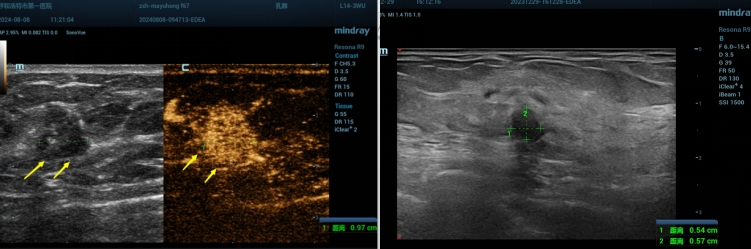

02病例:

患者女性,65岁,来我院就诊发现右乳低回声结节,行乳腺超声及超声造影检查后评估为BI-RADS 4C类,建议穿刺活检,术后病理证实为多发导管内癌。